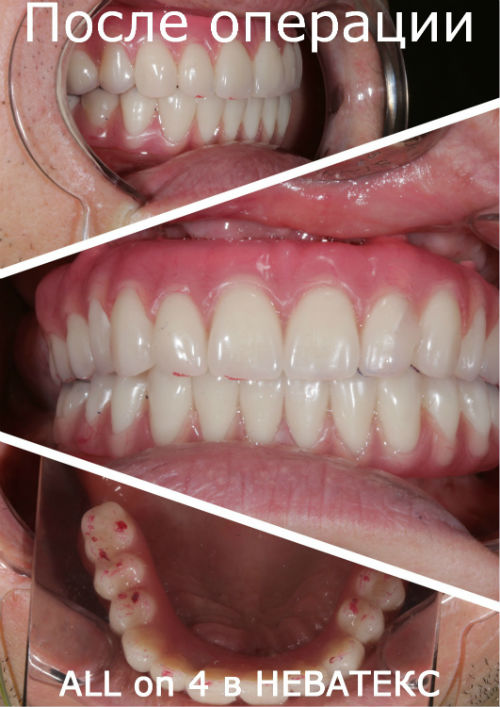

Зубы за один день фото до и после

Работа сделана в 2012 году

Как выглядит результат в день имплантации

Фото сразу после операции "зубы за 1 день"

Имплантация: фото ДО и ПОСЛЕ

Эти красивые зубы по протоколу ALL ON 4 установлены на 5 й день после операции и включены в стоимость